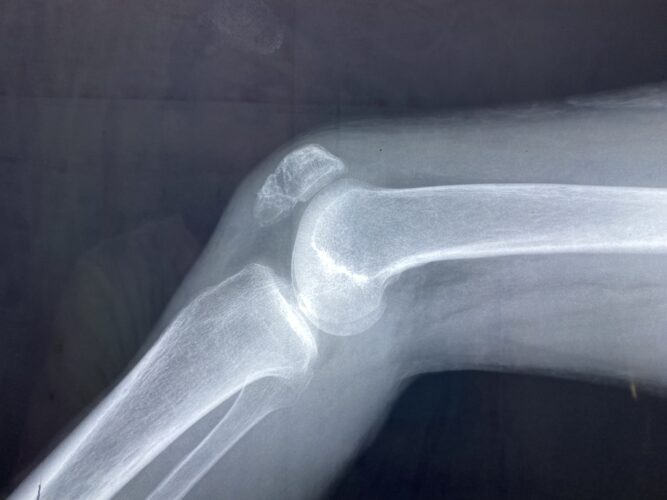

保存療法を選択した場合の上腕骨顆上骨折(伸展型)の特徴や注意点について